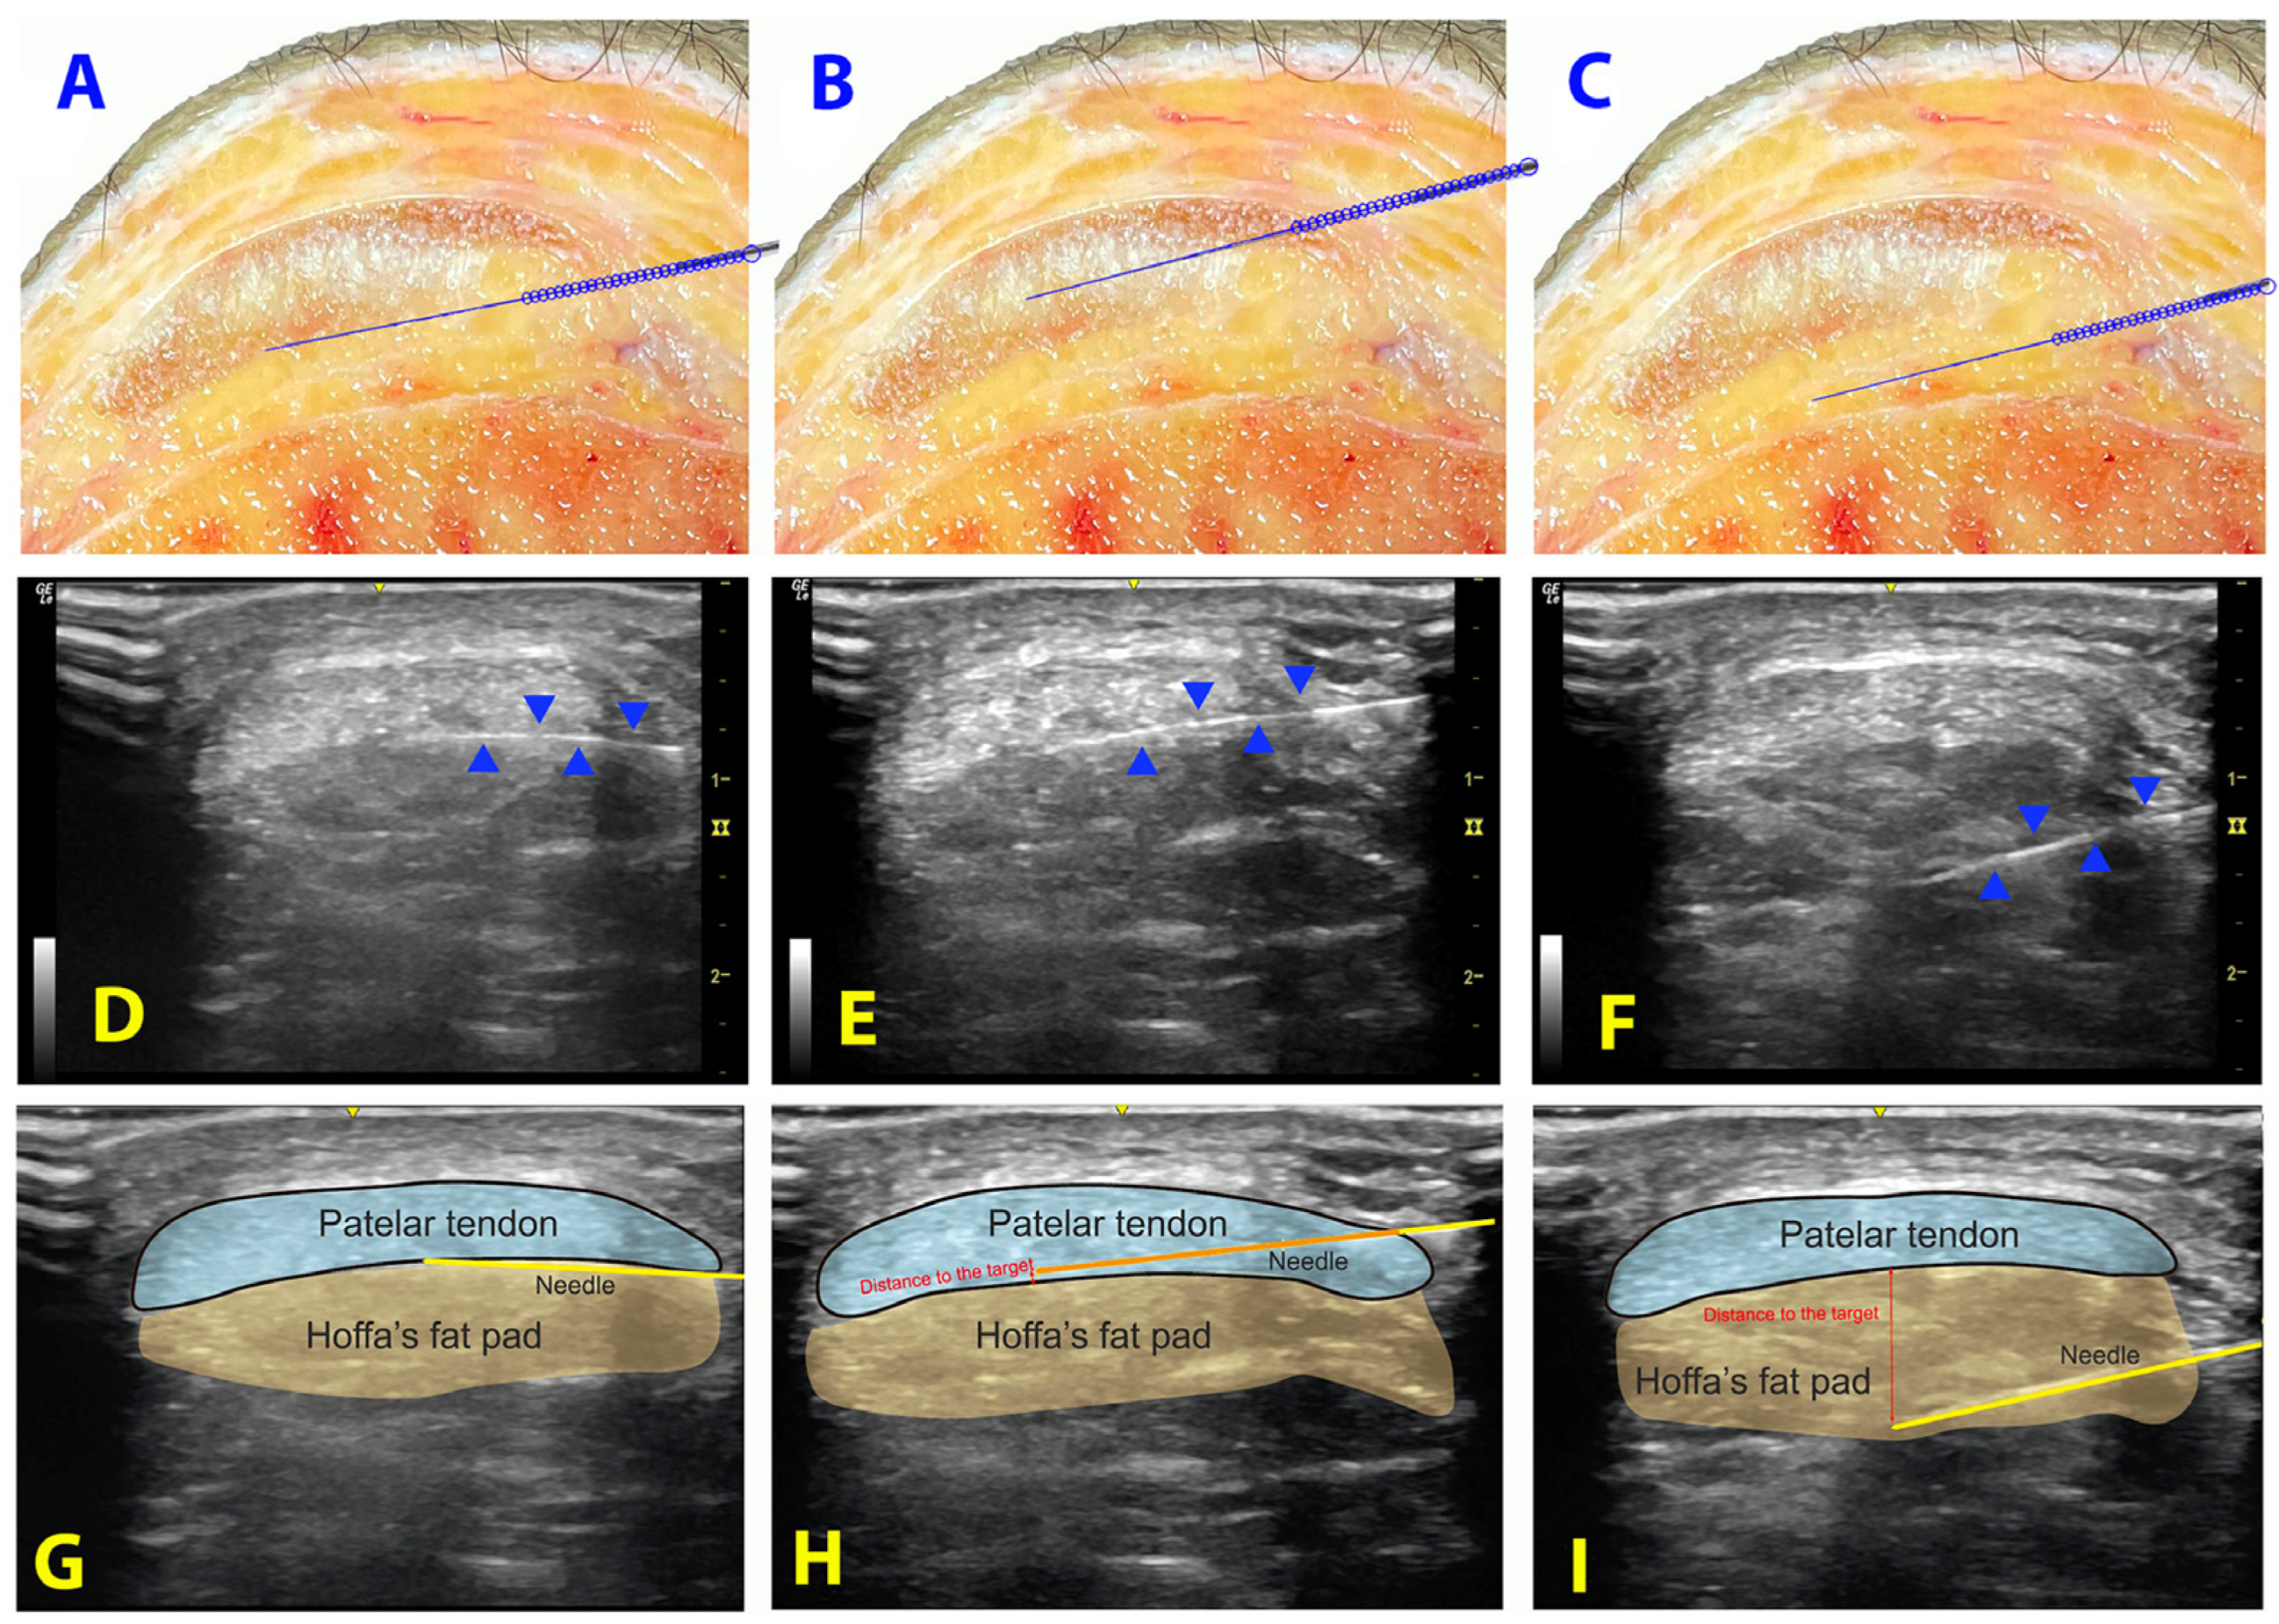

2.2. Procedure

- Distance: Distance of the needle’s tip to the target (in millimeters).

- Target contact and surface of contact: Contact of the needle with the interface between patellar tendon and Hoffa’s fat pad (yes/no) and the distance of contact (in millimeters).

- Punctured structure: If a different structure was punctured (patellar tendon or cortical bone). If the patellar tendon and not the interface was punctured, the distance from the needle to the interface between patellar tendon and Hoffa’s fat pad was recorded (in millimeters).

- Accuracy: The inserted attempt was considered accurate if the tip of the needle was properly placed less than 3 mm from the target or the contact with the interface was properly achieved.